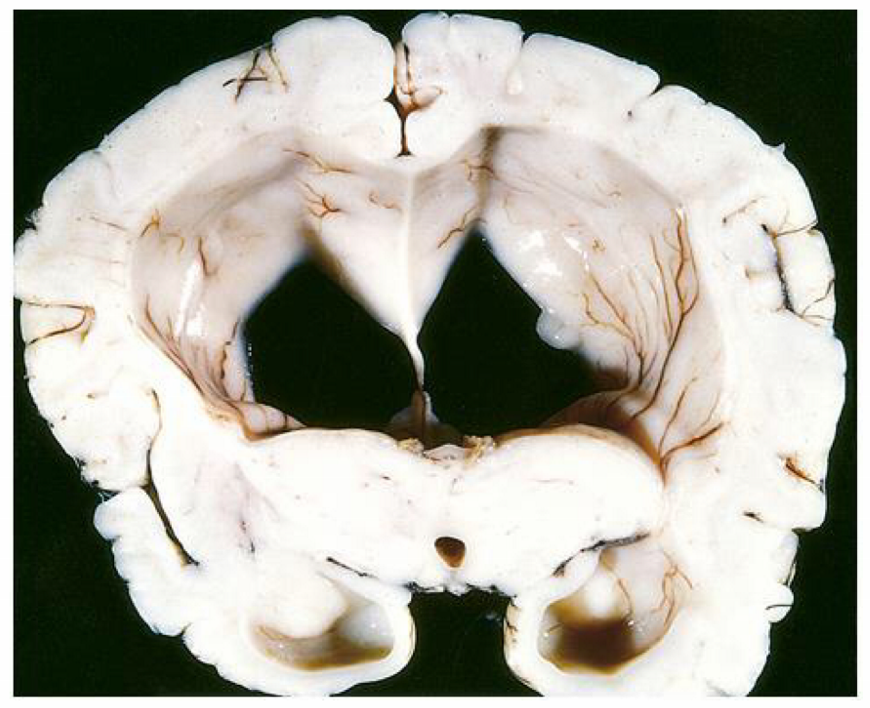

in the communicating form of the condition seen in the image, there is dilation of ___

in the communicating form of the condition seen in the image, there is dilation of ALL ventricles

the communicating form of the condition seen in the image can due to scarring/fibrosis of ____ or ____

the communicating form of the condition seen in the image can due to scarring or fibrosis of the arachnoid villi d/t tumors or infxns (TB, meningitis) or subarachnoid hemorrhage

the communicating form of the condition seen in the image is caused by reduced ____, such as in ____

the communicating form of the condition seen in the image is caused by reduced CSF resorption, such as in arachnoid fibrosis

the normal pressure form of the condition seen in the image is characterized by the triad of:

wet = urinary incontinence

the ex vacuo form of the condition seen in the image causes dilation of ____ due to ____ and causes a compensatory ____

the ex vacuo form of the condition seen in the image causes dilation of all ventricles due to cerebral atrophy and causes a compensatory increase in CSF

the non-communicating form of the condition seen in the image occurs between ____ & ____ or between ____ & _____

the non-communicating form of the condition seen in the image occurs between lateral & 3rd ventricle or between 3rd & 4th ventricle

the presentation of condition seen in the image in children is increased ____ because ____

the presentation of condition seen in the image in children is increased head circumference because skull bones (fontanelles & sutures) have not fused yet

the presentation of condition seen in the image in adults is increased ____

the presentation of condition seen in the image in adults is increased ICP